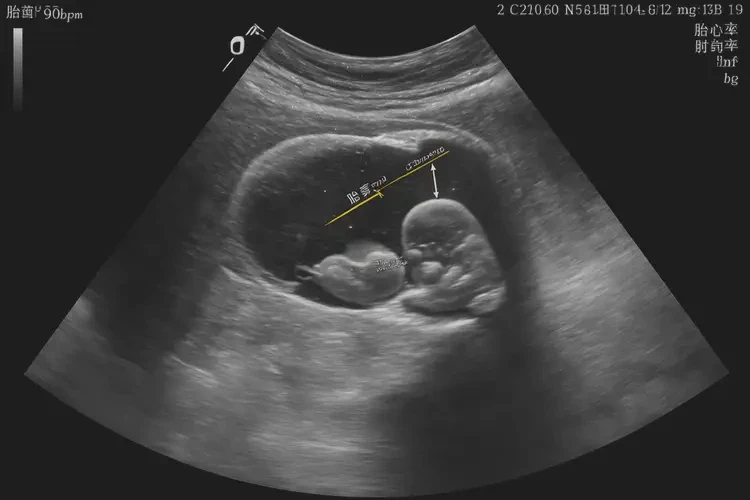

胎心率在怀孕20多天时通常在100-180次/分钟之间。

怀孕20多天时,胎心率在90次/分钟左右可能偏低,但需要结合具体情况来判断是否正常。以下是一些相关因素和建议:

- 早期胎心率:在怀孕6-8周时,胎心率通常在100-180次/分钟之间。

- 胎心率变化:胎心率会随着孕周的增加而逐渐下降,到怀孕12周左右会稳定在120-160次/分钟之间。